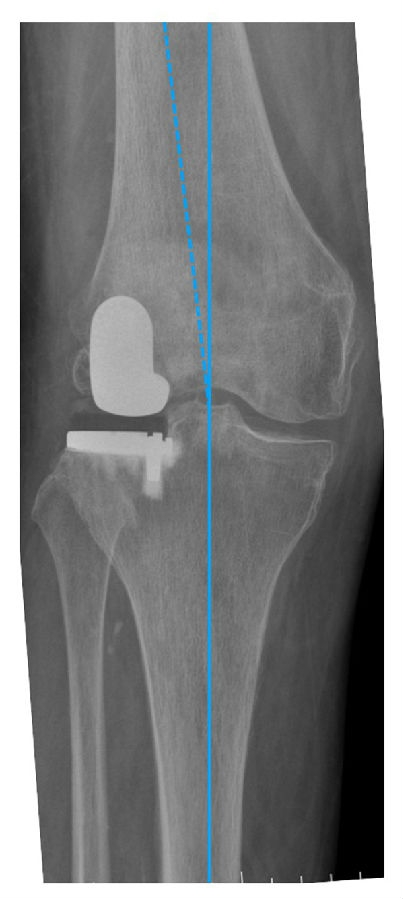

关键技术3:理想的下肢力线

HIP-Knee-Ankle line 外翻3-5°,胫骨角10-12°

LUKA 术后畸形矫正不足,保持轻微的外翻。建议LUKA术后保留3 ~ 5°外翻。

理想假体位置 A.股骨假体 胫骨假体中心线一致;B.股骨假体固定栓与后侧皮质呈35-40°

理想假体位置即前缘平稳过渡,后缘包容很好且不超出。